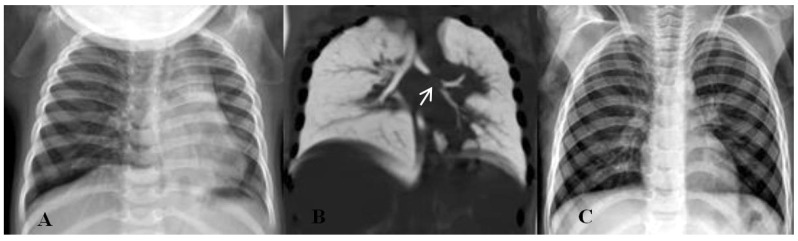

Abstract Image